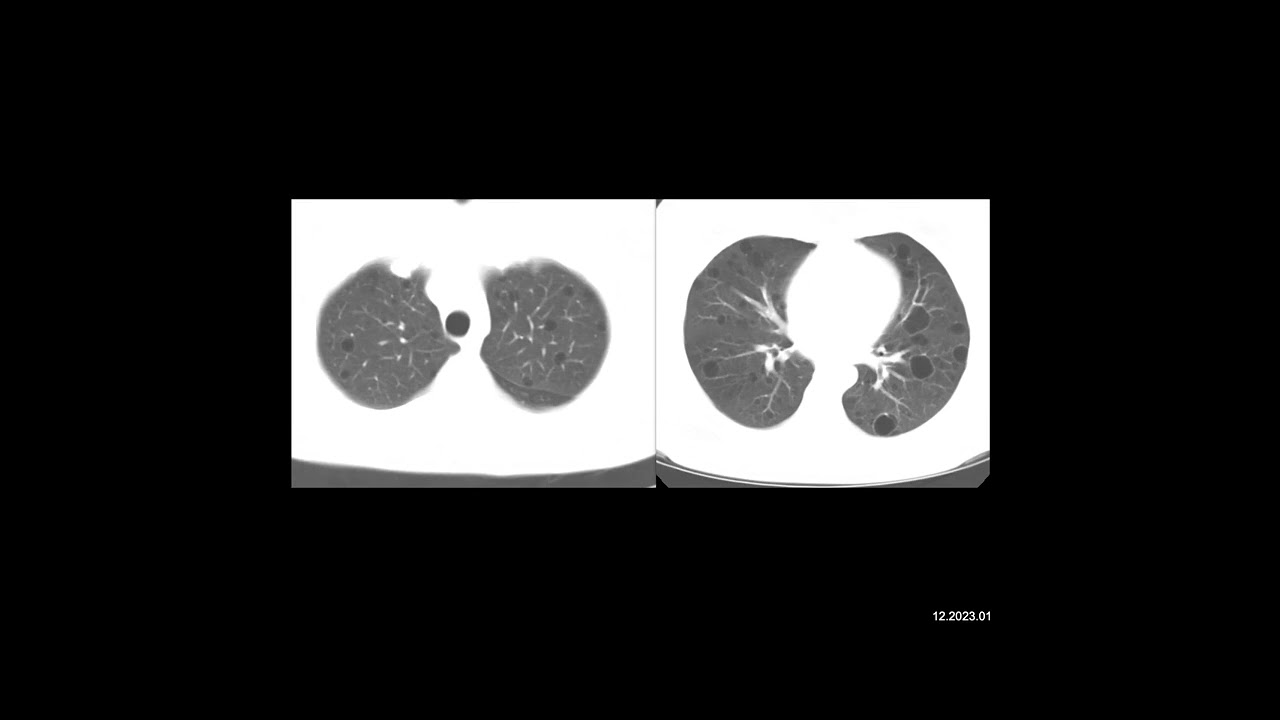

Муковисцидоз у женщины 34 лет. Помимо нерезко выраженного усиления воздушности легких на рентгенограмме грудной клетки виден тяжистый рисунок, охватывающий все легочное поле и особенно выраженный в верхнем и среднем его отделах. Корни легких укорочены и смещены кверху. Эти признаки обусловлены выраженными изменениями бронхиальной стенки и бронхоэктазами.

КТ более информативна для определения типа и объема изменений. На срезах, проходящих через легкие, видны многочисленные кистовидные и мешотчатые бронхоэктазы